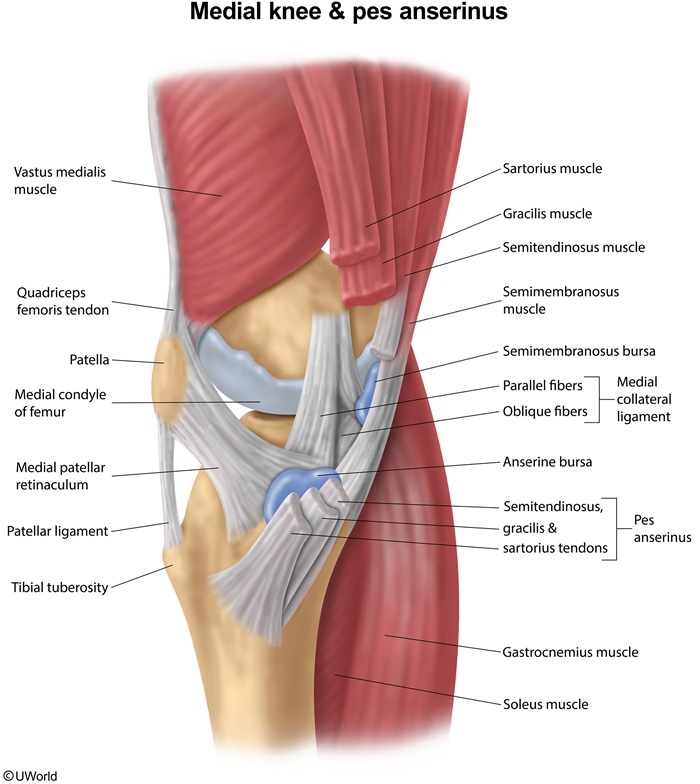

Pes Anserine Bursitis

This patient with medial knee pain and focal tenderness has pes anserinus pain syndrome (PAPS). This condition is often referred to as anserine bursitis, but most patients do not have true inflammation in the bursa, and multiple regional structures can contribute to the pain. The pes anserinus is formed by the conjoined tendons of gracilis, sartorius, and semitendinosus. The anserine bursa is located anteromedially over the tibial plateau, just below the joint line of the knee and deep to the pes anserinus.

PAPS can be caused by an abnormal gait, overuse, or trauma. Localized pain is typical over the anteromedial tibia and is often exacerbated by pressure from the opposite knee while lying on the side. Examination shows a well-defined area of tenderness over the medial tibial plateau just below the joint line. A valgus stress test does not aggravate the pain, indicating no medial collateral ligament involvement (Choice A). The diagnosis is primarily based on clinical features, although x-ray can exclude concurrent osteoarthritis of the knee.